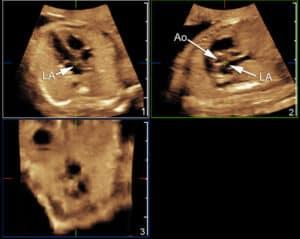

Explore the advancements in fetal heart imaging with volumetric techniques like 3D and 4D ultrasound. This guide covers the principles, technologies, and clinical applications of volumetric imaging in fetal echocardiography. Learn about transducer technology, volume acquisition, and visualization methods used to assess fetal heart defects, such as D-Transposition of the Great Arteries, Hypoplastic Left Heart Syndrome, and Ebstein Anomaly. Discover how STIC (SpatioTemporal Image Correlation) and rendering technologies enhance diagnostic accuracy, and how these tools are utilized in clinical practice and telemedicine for diagnosing congenital heart disease.

recognize examples of common cardiac anomalies as depicted by volumetric imaging